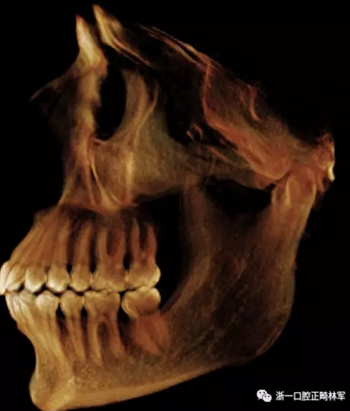

在輸出的3D模型上,使用體內(nèi)軟件(Anatomage,San Jose,Calif)將下頜骨以最小的間隔從顱骨上分離(圖5)用于保留下頜骨的咬合細(xì)節(jié),游離的下頜骨被保存(圖6,A)。同時,將沒有下頜骨的顱骨導(dǎo)出并保存(圖6,B)。

圖6. A,從整個3D模型上修剪的下頜骨; B,修剪的顱骨。